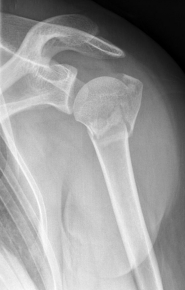

Picture: Here is a subcapital upper arm break in a young woman. An angle stable plate osteosynthesis was performed to stabilize the head in correct position to the humeral shaft and shoulder joint. Especially in young patients, We strive to treat non-invasively and as gently as possible. This possibility is often due to the bone quality in young as opposed to older people.